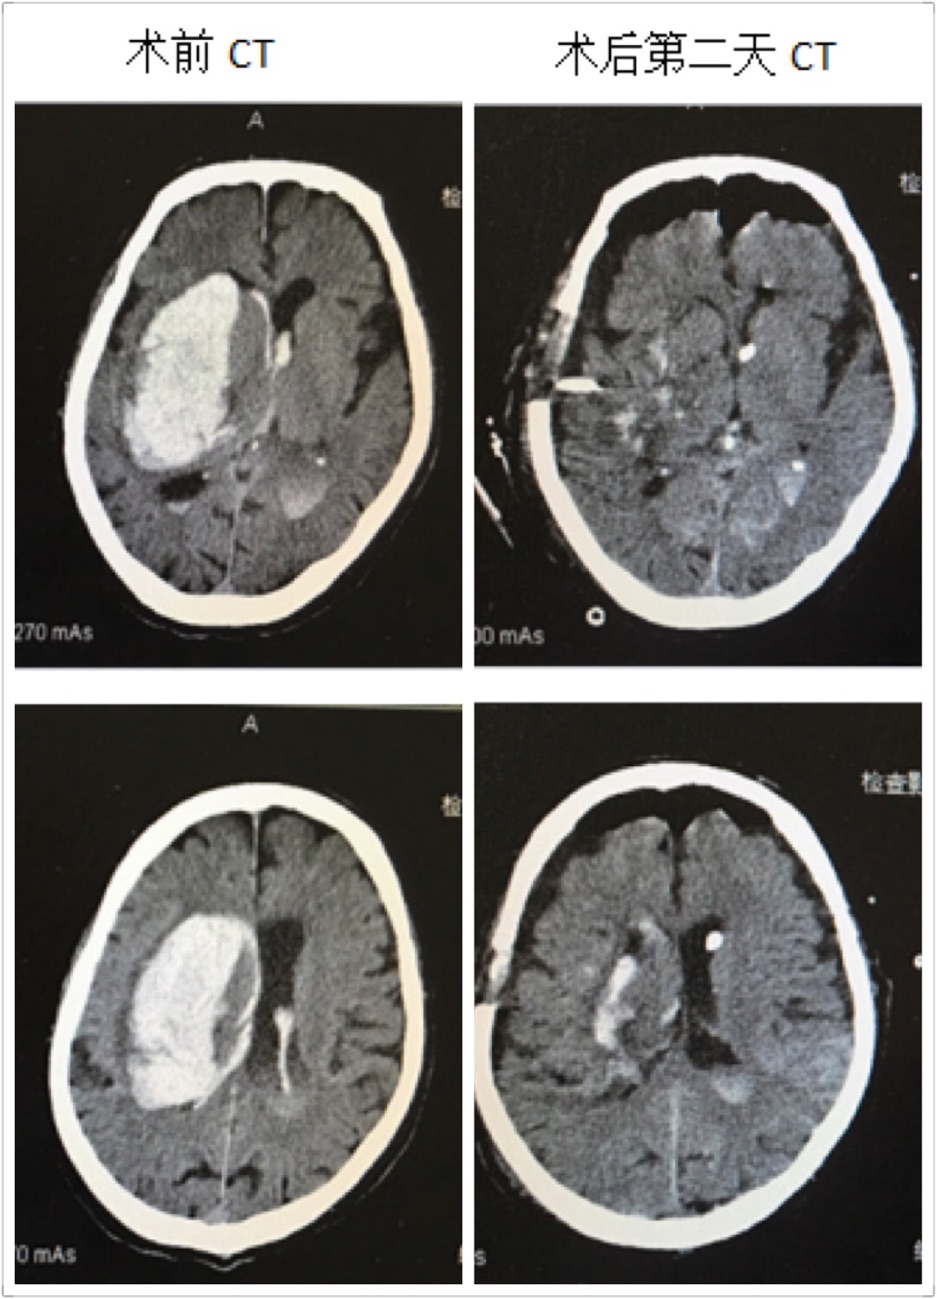

近日,成人导航 神经外科成功救治一名高龄脑出血患者,并顺利康复出院,取得了满意的疗效。这位男性患者86岁,出血量约120ml,入院后处于深昏迷状态,Glasgow评分仅3分,一侧瞳孔散大,颅内高压频繁喷射性呕吐,病情危重,随时有死亡的可能。在这例高龄脑出血患者入院后,成人导航 神经外科王钢副主任医师放弃休息时间,立即组织医疗小组,商讨治疗方案,像这样大量脑出血手术必须手术治疗。在保证血肿清除率及创伤小、出血少的前提下,在我科完成多例神经内镜下血肿清除术的基础下,王钢副主任医师提出:这位高龄患者可以采取小骨窗和神经内镜下清除血肿。

在王钢副主任医师的带领下,和麻醉科曹淑梅主任,杨克副主任一起,经过详细的术前讨论,制定周密的手术方案,急诊在全身麻醉下行脑出血小骨窗及神经内镜下清除血肿。手术十分顺利,手术历时2小时,骨窗大小直径约3cm,术中完全清除血肿,出血极少,术中未输血。术后第2天患者意识状态明显好转,由昏迷转为呼唤睁眼,出院时患者意识已经清醒,并且能够正常交流。